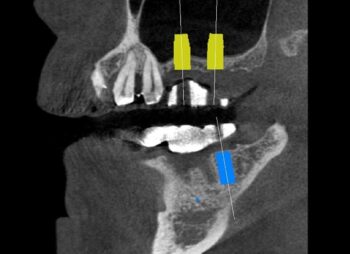

サイナスリフト(上顎洞挙上術)

サイナスリフトとは

サイナスリフトは、上顎の奥歯にインプラントを埋め込むにあたり、土台となる骨の量を増やす治療法の一つです。

サイナス(上顎洞)とは上顎内部の空洞のことです。上の奥歯を失ってしまうと、このサイナスと呼ばれる空洞が拡大し、結果的に上顎の骨が薄くなってしまいます。こうなると、インプラントを埋め込むのに十分な骨の厚さを確保することができません。

サイナスリフトは、このように骨が薄くなってしまった場合に、外科手術によって歯肉を切開し、空洞の拡大した部分に移植骨を入れて埋めていく骨造成法です。手術から3~6ヶ月ほどで、移植した骨が完全に自分の骨となり、インプラントを埋め込むことが可能になります。